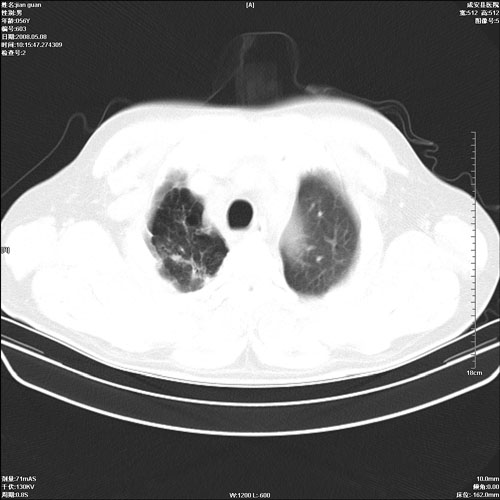

病人 男 60岁 主诉 胸闷 无明显发热 一般情况尚可。

肺结核?

两上肺陈旧性结核;慢支肺气肿、伴感染?

考虑1心功不全,肺水肿

2右上肺结核纤维性病灶、肺气肿

1.右上肺陈旧性肺结核.

两上肺陈旧性结核;慢支肺气肿

1.两上肺陈旧性结核;慢支肺气肿。

考虑.两上肺陈旧性结核;慢支肺气肿。肺心病

两上肺陈旧性结核,慢支肺气肿。

两上肺陈旧性结核;慢支肺气肿。肺肺间质纤维化

两上肺陈旧性结核;慢支肺气肿。

1.陈旧肺结核;

2.慢支肺气肿;

3.肺心病.